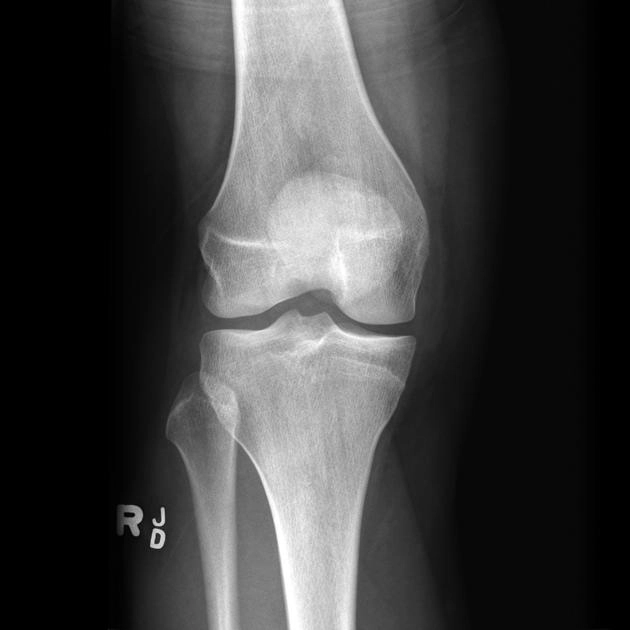

Rách dây chằng chéo trước ACL (Anterior cruciate ligament tear)

Tổn thương dây chằng bên trong (Medial Collateral Ligament - MCL injuries)

Phân độ tổn thương dây chằng bên trong (Medial collateral ligament injury grading)

Tổn thương dây chằng bên ngoài (Lateral collateral ligament injury of the knee)